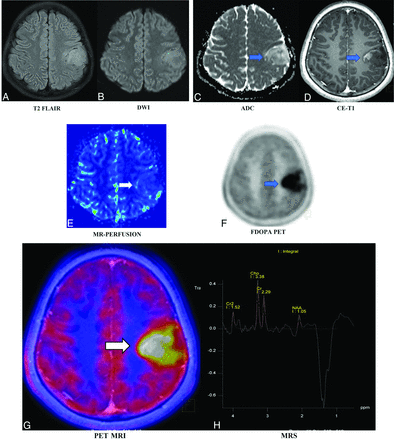

A 12-year-old boy presented with right focal seizures for a month. Electroencephalography was noncontributory. Imaging-based diagnosis of a tuberculoma was made on the initial contrast-enhanced MR imaging in November 2019. Antitubercular treatment was started empirically. Follow-up MR imaging in February 2022 showed an interval increase of the mass from approximately 1.5 × 1.3 cm to 3.8 × 3.6 cm (images not shown), which led to further work-up, and the patient underwent AA-PET MR imaging and FDOPA-PET MR imaging. T2 FLAIR (A) demonstrates a hyperintense left posterior frontal mass with equivocal diffusion restriction on the diffusion-weighted image (B and C, blue arrow). A predominantly nonenhancing mass with small peripheral nodular enhancement is seen on postcontrast T1-weighted image (D, blue arrow). No apparent increased regional CBV is seen on DSC PWI (E, white arrow). On FDOPA-PET (F, blue arrow) and fused FDOPA-PET MR imaging (G, white arrow), the lesion showed uniformly increased DOPA uptake throughout with a high maximum standard uptake value of 3.62 (lesion/striatum ratio of 1.81 versus <1.0 as normal) and TBR. Multivoxel MRS (H) showed Cho/NAA and Cho/Cr ratios of 2.78 and 1.4, respectively, with a prominent lactate peak. In this patient, FDOPA-PET MR imaging confirmed the precise diagnosis of neoplastic etiology, which, on biopsy, was revealed to be an anaplastic astrocytoma. CE indicates contrast-enhanced.